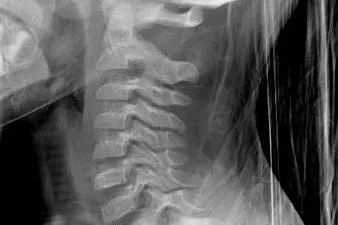

Normalt sidebilde.